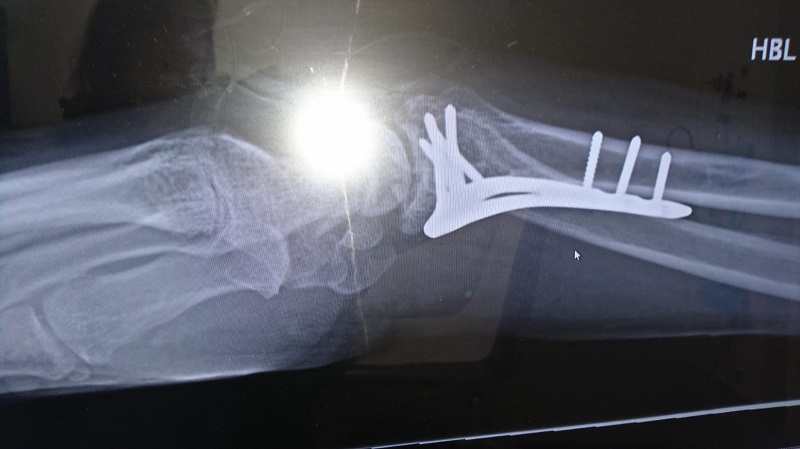

Up to hospital and after my arm was pulled back into shape without anaesthetic, my screams of pain clearing the department, my left arm had a Smiths or Collies fracture and would need some metal work, my right could be casted but was borderline. Wishing to wipe my own bum I opted not to. But finally I had the morphine and I could relax enough to make jokes about how all this was going to make a great story and I couldn't look up to Geraint Thomas because he's a Cardiff City Fan. I also asked how long I'd be off the bike. Answer minimum 12 weeks.

So I'm still a little broken. Flash backs to the crash and the manipulation keep me awake. The CRPS makes an uncertain future. But I'm not beaten I have a cool metal arm. I'm training as a race commissaire and I still have that great hat.